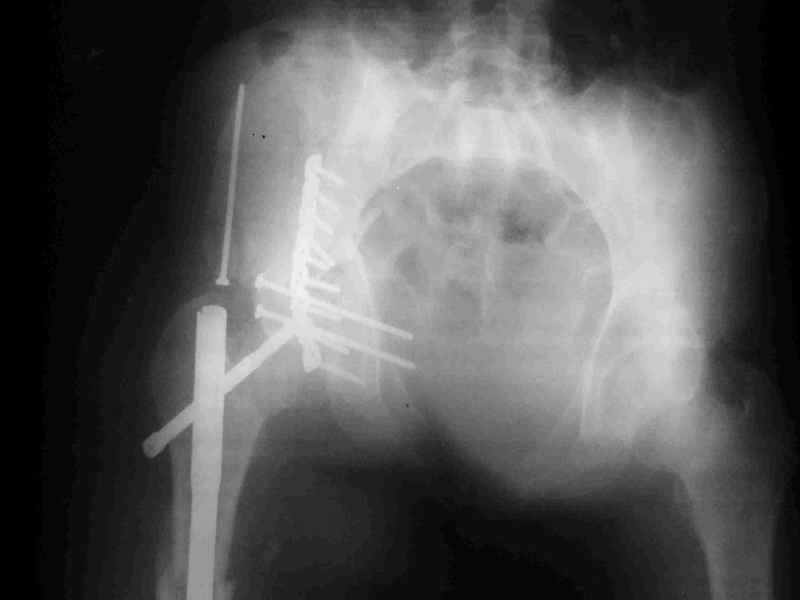

перелом крыла правой подвздошной кости, перелом обеих колонн вертлужной впадины, двусторонний перелом лонных костей (С2.2) повреждение передних связок правого крестцово-подвздошного сочленения,

ипсилатеральный перелом шейки и диафиза бедра.

К сожалению, набора для ретроградного или антеградного реконструктивного штифтования в операционной нет, поэтому доставка заняла н-ное время. Вопрос, который возник у меня- по поводу оптимальной тактики хирургии: вся фиксация в один этап из расширенного доступа или последовательно сначала бедро и позже реконструкция впадины, комбинированный доступ к впадине отдельно к передней и задней колоннам или из расширенного илеофеморального одного доступа. Все-таки решил остановиться на одноэтапном подходе и спустя 5 дней (как раз и наборы привезли) из расширенного илеофеморального доступа сначала фиксировал реконструктивным штифтом Smith&Nephews бедро и

шейку (благо перелом шейки 2 типа -относительно стабильный) затем фрагмент крыла подвздошной кости Lag screw, далее пластина на заднюю колонну и винты в переднюю колонну.(с размерами и направлением винтов ошибка вышла:-((, но интраоперационно у меня была полная уверенность , что винты *ушли* в лонную кость).